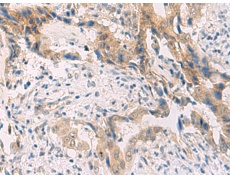

IHC positive control: |

Human cervical cancer and Human prostate cancer |

IHC Recommend dilution: |

40-200 |